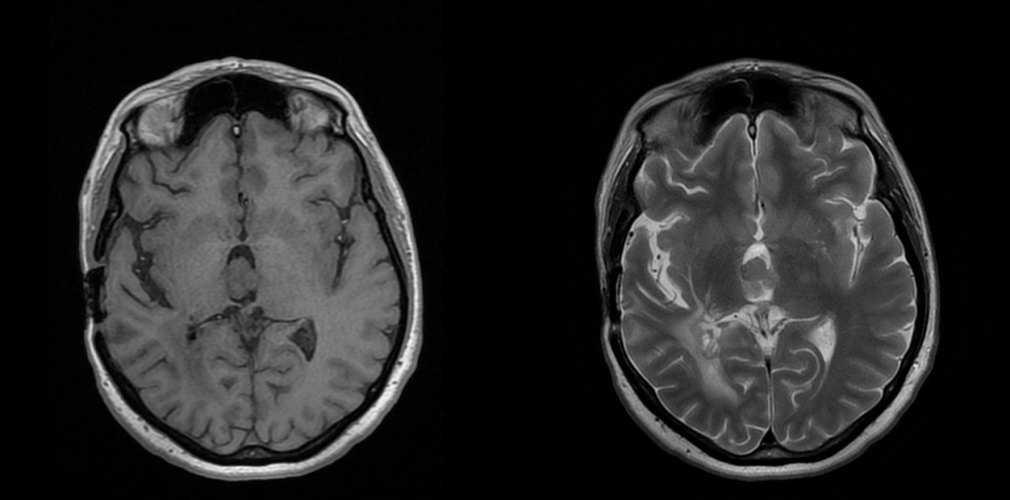

– Investigații imagistice: RMN (rezonanță magnetică) și/sau CT (tomografie computerizată), care evidențiază masa tumorală și hidrocefalia asociată

Tumorile apar de obicei în ventriculul lateral la copii, iar în ventriculul IV la adulți, deși există multiple excepții.